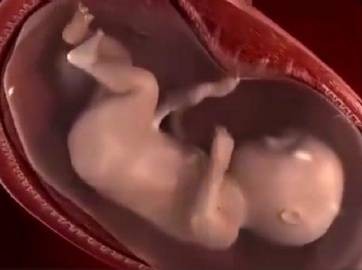

妈妈从孕育到孩子的出生,中间要经历10个月。网上有一组生动形象的动图,可以看出这十个月妈妈究竟经历了什么,这个期间,宝宝每个月在妈妈的肚子里的状态都是不一样的。如果有看过一个胎儿从开始孕育到出生10个月的不同形态,你就会感受到生命的神奇,宝宝在妈妈肚子里每个月不同的形态。

孕妈在怀孕第五个月的时候,此时肚子就已经很大了,在肚脐眼下方很容易能够摸到子宫,此时的子宫变得很大。

怀孕六个月时,孕妇的肚子隆起得很明显,而且子宫会挤压内脏,会让孕妈出现胸闷、呼吸不畅的一些现象。

孕妈在怀孕第七个月的时候,孕妇吃的东西会越来越多,体重上升增幅很大,这是因为胎儿在这个时期需要吸收更多的营养来供自己成长,在这个时候最忌讳的就是孕妇节食。